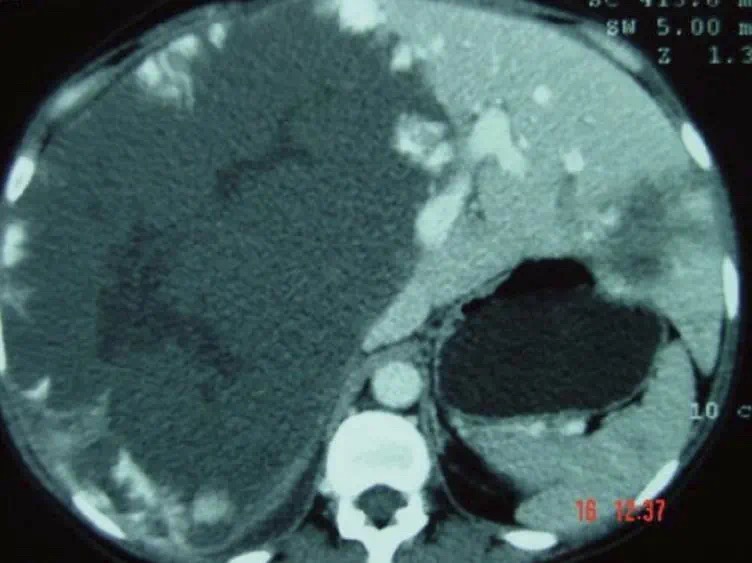

患了肝血管瘤,你准备怎么办?

日期:2021-04-23